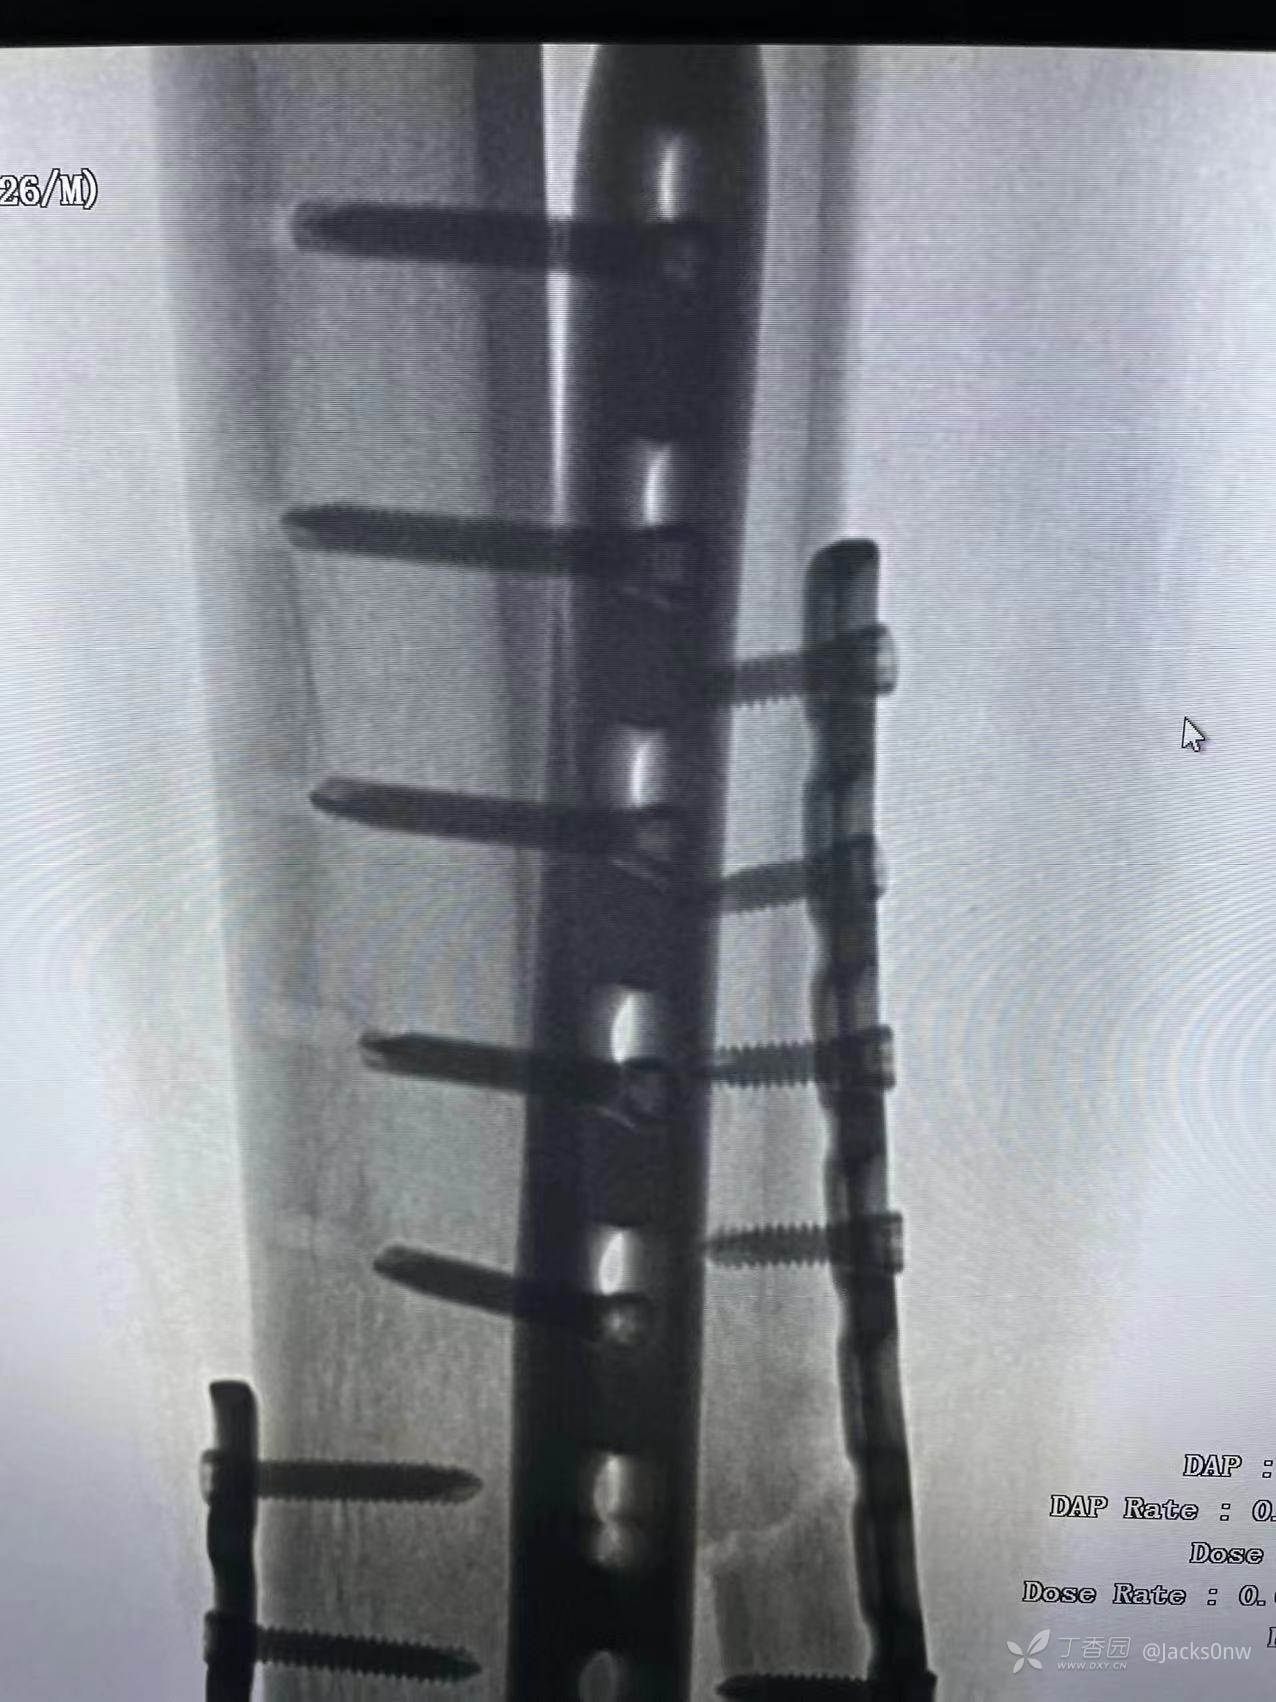

术中

2022年10月26 14时行左胫骨远端(Pil0n)粉碎性骨折切开复位钢板螺钉内固定术+左腓骨中下段粉碎性骨折切开复位钢板螺钉内固定术+神经血探查术+骨筋膜室综合征切开减压术+骨移植术+高分子夹板外固定术。